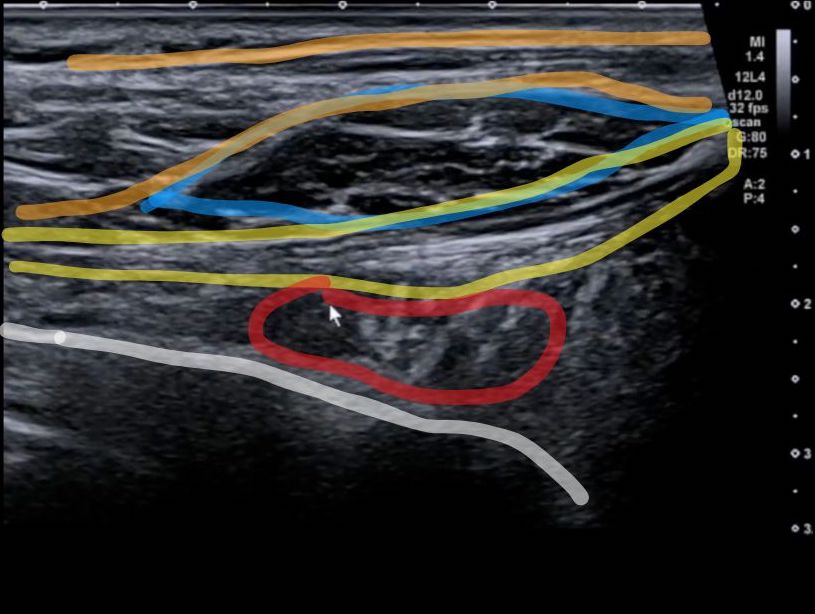

頸長肋筋のエコー画像

頸長肋筋は、超音波(エコー)で確認することができます。

茶:僧帽筋

青:肩甲挙筋

黄:上後鋸筋

赤:頸長肋筋

白:第2肋骨